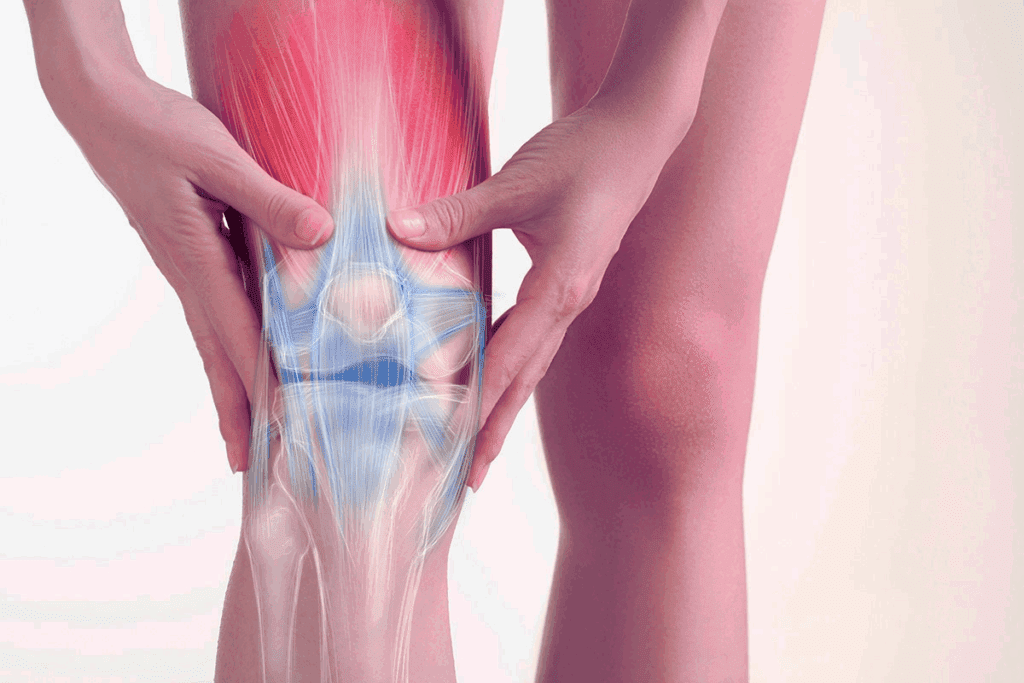

The knee is more than a simple hinge joint. It’s a complex structure with bones, ligaments, and muscles. It helps us bend and straighten our knee. It also absorbs shock and supports our body weight.

| Knee Movement | Primary Muscles Involved | Function |

| Flexion | Hamstrings | Bending of the knee |

| Extension | Quadriceps | Straightening of the knee |

Understanding the knee’s mechanics is important. It helps us see its role in our body’s function. It’s also key for creating good plans when we get knee injuries.